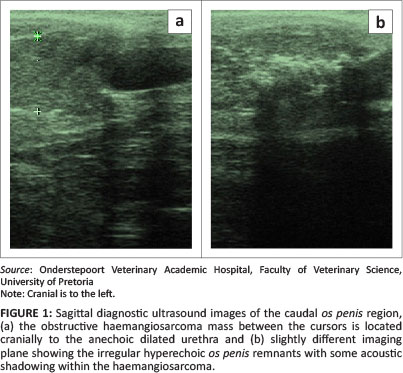

A 9-year-old intact boerboel cross-breed dog was presented with a month-long history of stranguria and pollikuria. The patient had been examined by the referring veterinarian and had been treated with antibiotics. On clinical evaluation, a large bladder and a spherical swelling at the caudal aspect of the os penis were detected by palpation. Routine urinalysis, haematology and serum biochemistry were unremarkable. Abdominal and penile ultrasound was performed (Siemens Sonoline Omnia, Siemens, Germany). Abdominally, the only abnormalities detected were a distended bladder and pelvic urethra. The urethra was tracked transcutaneously along the length of the penis up to the level of the os penis where an extramural obstructive, roughly spherical 13.7 mm by 14.3 mm mass was seen. It was completely compressing the urethral lumen, resulting in distension of the urethra caudal to the mass (Figure 1). The mass was hyperechoic relative to the adjacent soft tissue and a number of irregularly shaped small hyperechoic specks were seen with associated distal acoustic shadows indicative of mineralisation (Figure 1). The mass appeared to involve the parenchyma of the penis and was suspected to have arisen extramurally, invading the urethral lumen. Colour flow Doppler (Siemens Sonoline Omnia, Siemens, Germany) indicated significant vascularity within the mass and on its periphery. The surface of the os penis was irregular and undulating with varying thickness, indicative of a periosteal reaction and lysis. A neoplasm of the penis, the os penis or surrounding tissue was suspected. Fine needle aspiration of the mass and cytology indicated a poorly differentiated sarcoma, ostensibly an osteosarcoma. Metastatic lung and lateral radiographs centred and collimated over the os penis were made. Thoracic views were normal. Radiographs of the os penis demonstrated a single, spherical soft tissue opacity located over the caudal half of the os penis. It was associated with moderate lysis of the os penis and a sparse brush-like to sunburst periosteal reaction (Figure 2).